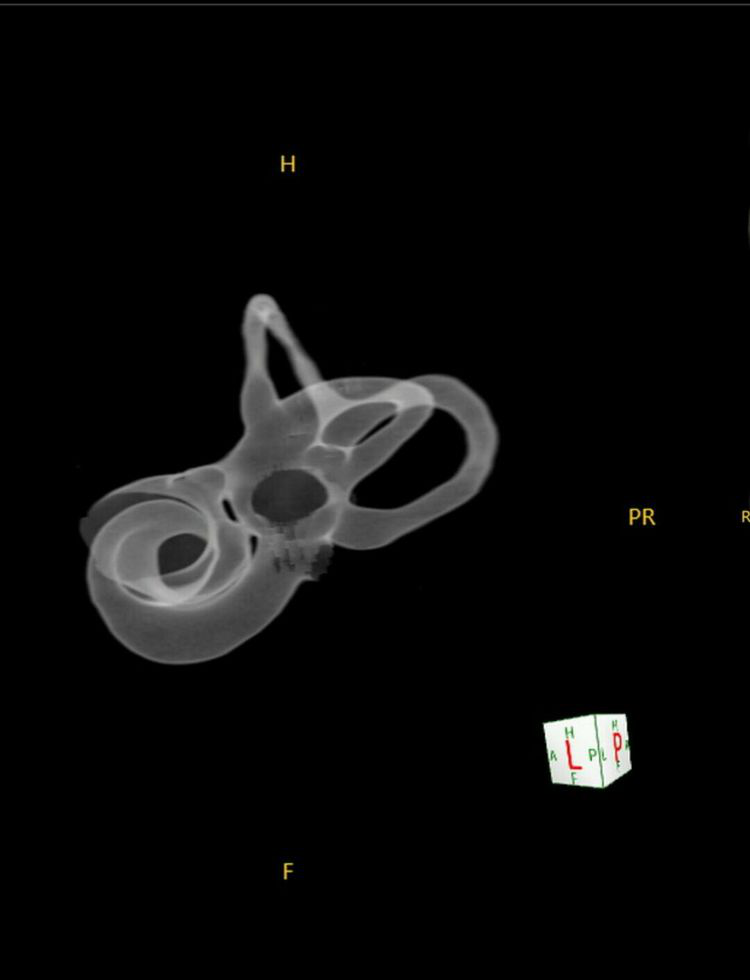

四.五官:

1024 大矩阵成像技术对于精细结构,如内耳、眼部等小器官、小病变具有更高清晰度和准确性。